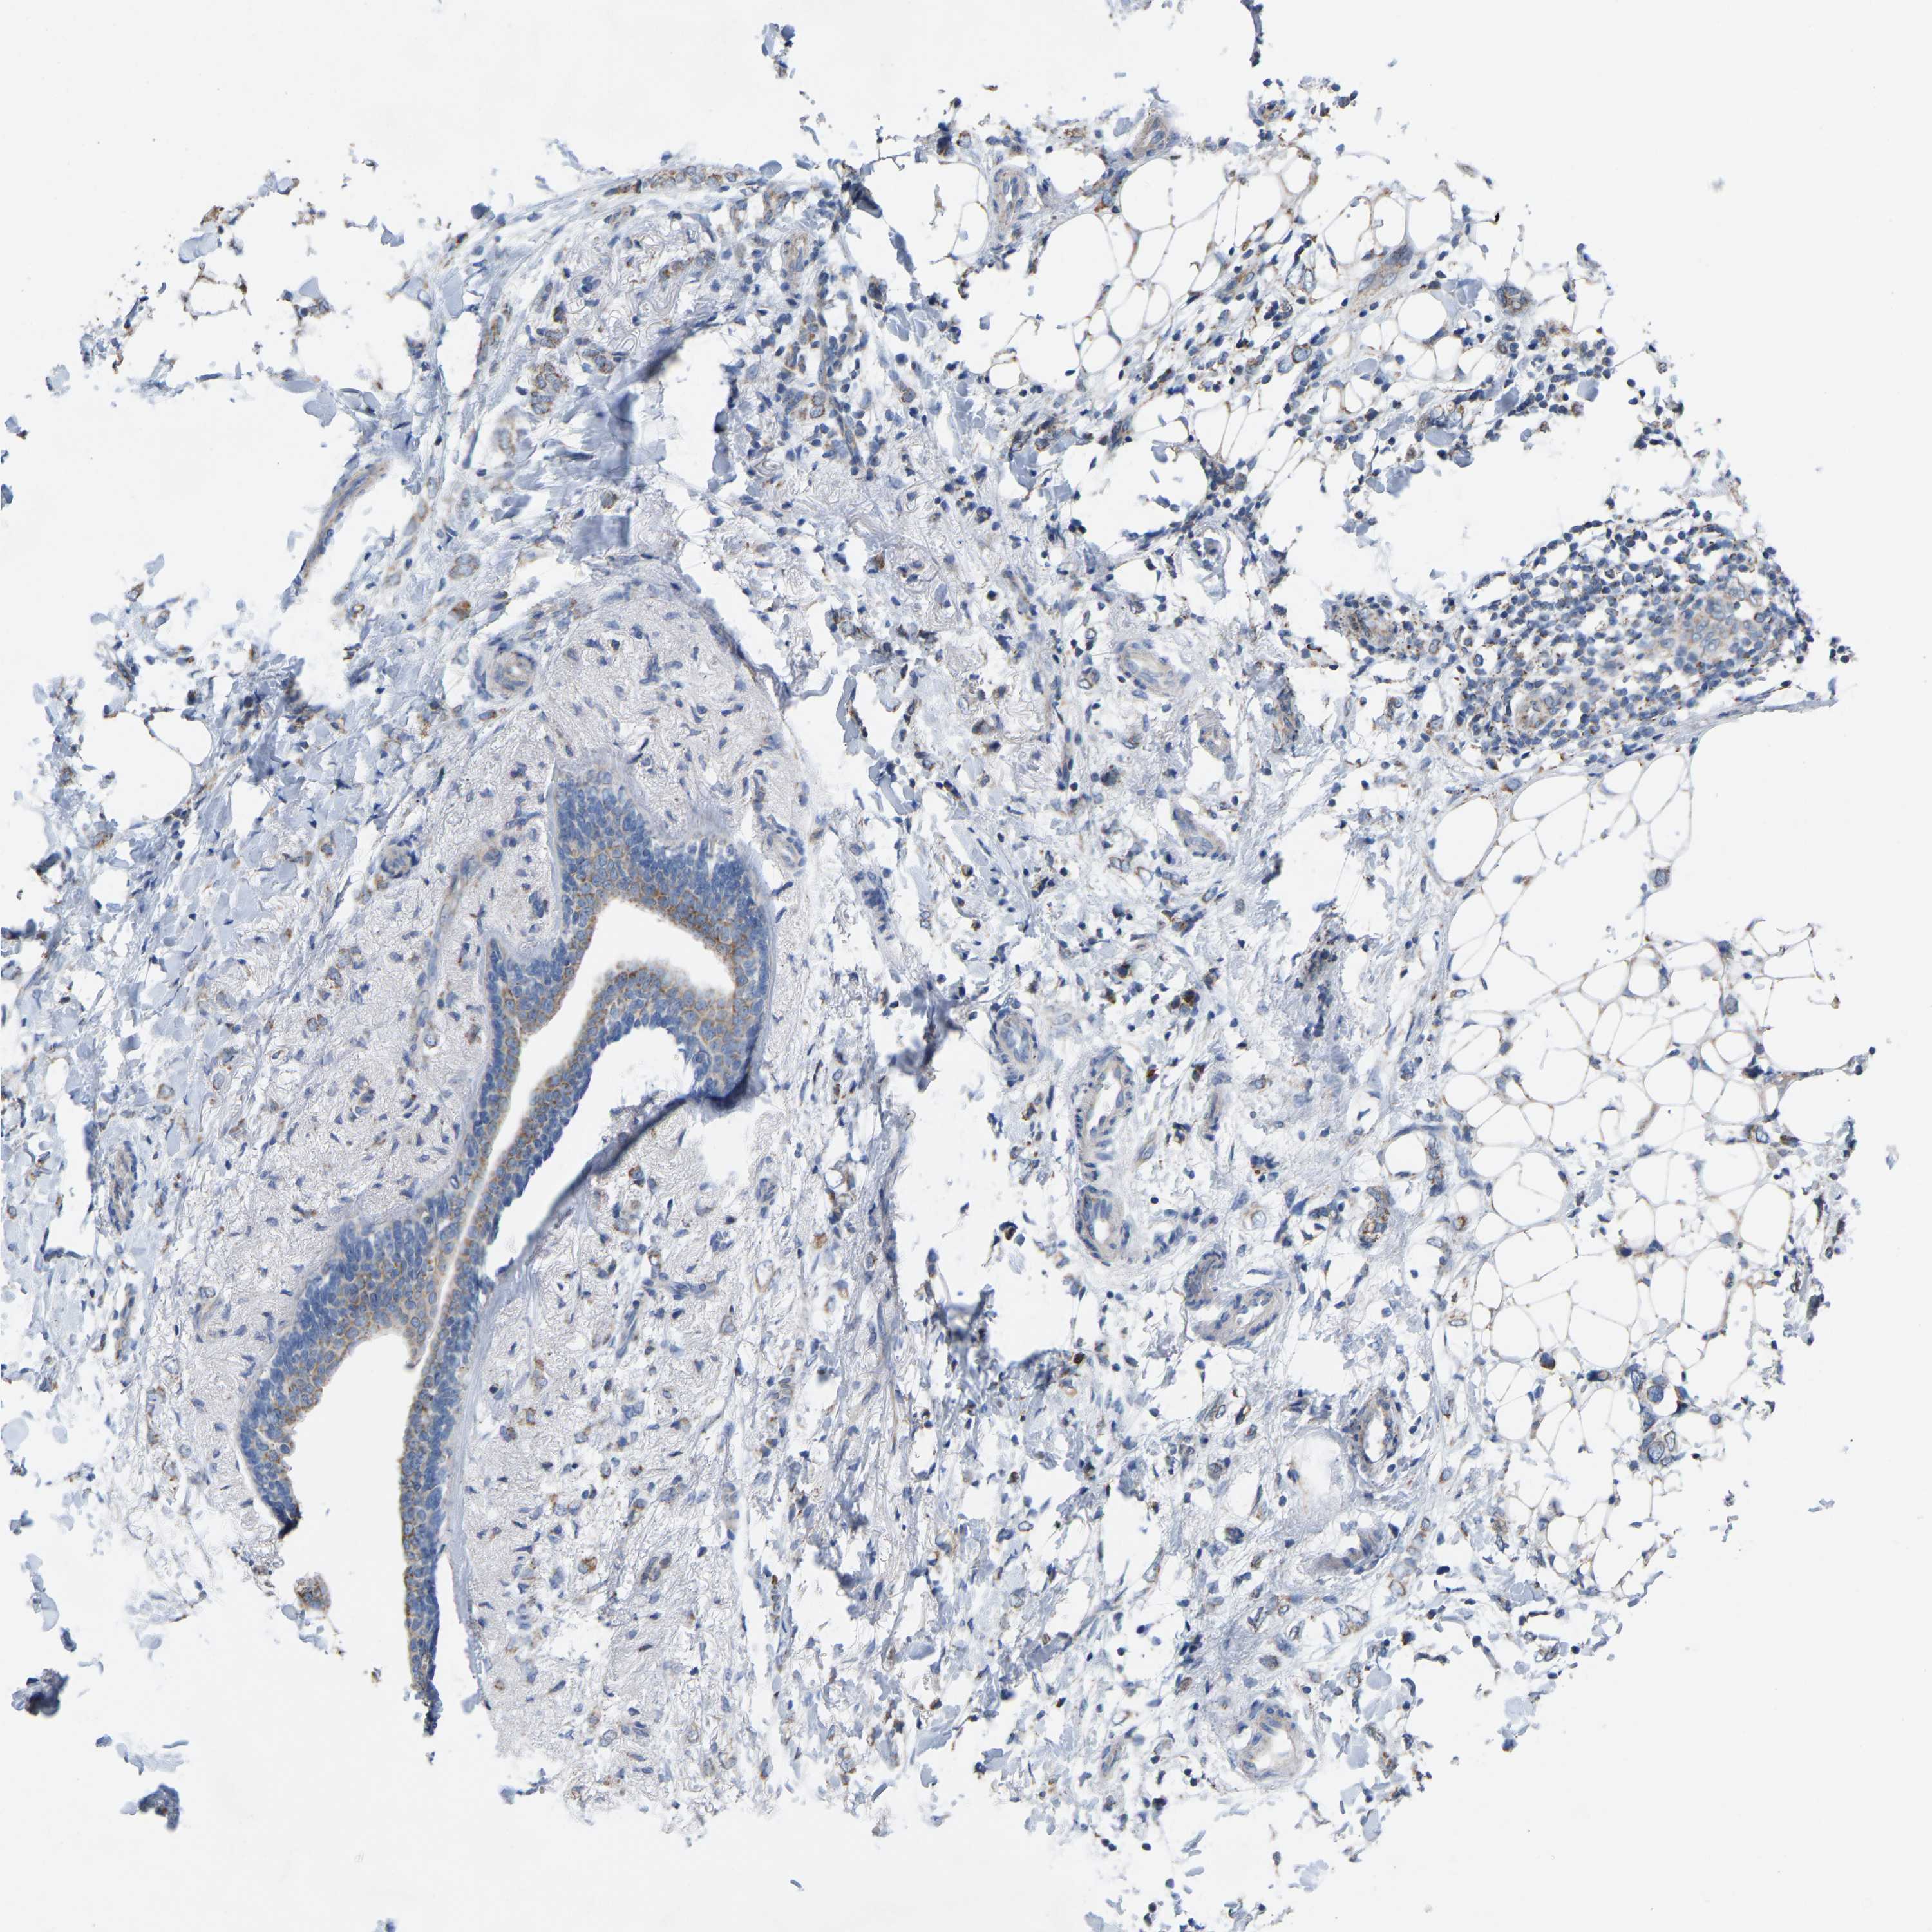

CANCER BREAST CANCER Show tissue menu

BRCA TCGA BRCA VALIDATION PROTEIN EXPRESSION